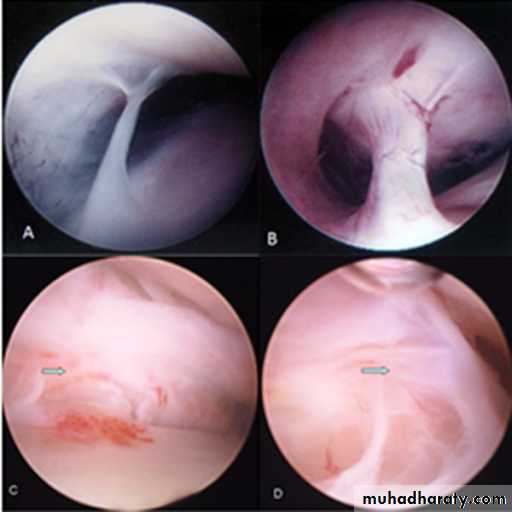

Arthroscopy

• Arthroscopy allows visual examination of the upper joint space and an opportunity for minor surgical treatment. A small arthroscope can be used to facilitate lavage and division of joint adhesions.• The lower joint space is difficult to access without risk of damage to the articular disc.

• Arthroscopy is undertaken under local anaesthesia; however, if lengthy arthroscopic surgery is to be undertaken, then a conscious sedation technique would be appropriate or even general anaesthesia.

• Arthrocentesis

• Arthroscopy

Arthrocentesis involves lavage of the upper joint space, using hydraulic pressure and manipulation to release adhesions.

Arthroscopy: eliminate joint adhesions. Joint can be mobilized which itself may improve disc mobility. Arthroscopy can be used to release adhesions directly, to perform joint space lavage and to introduce steroids.